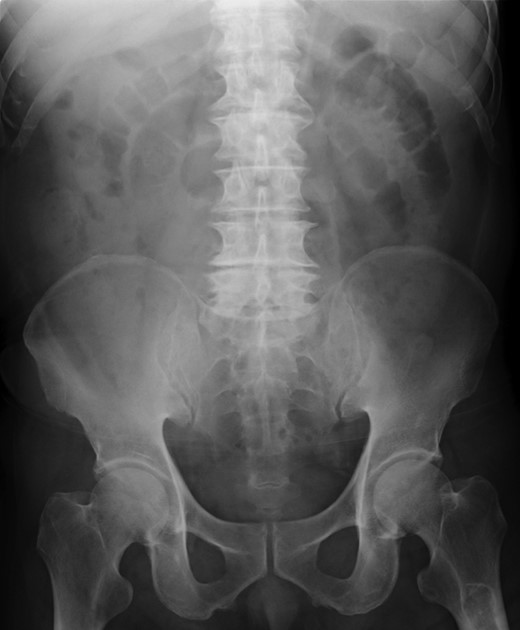

A 79-year-old man with acute abdominal pain had gone to a nearby hospital. As HPVG was detected by abdominal computed tomography (CT), he was transferred to our hospital for further examination and treatment. He had no remarkable past medical history. When he arrived at our hospital, his vital signs were relatively stable (body temperature: 37.2°C; blood pressure: 112/74 mmHg; pulse rate: 68 beats/min). However, physical examination revealed abdominal distention, rebound tenderness and abdominal guarding as signs of peritoneal irritation. The laboratory findings indicated acute inflammation (white blood cell count of 18 400/μL and Creactive protein concentration of 17.7 mg/dL), dehydration and metabolic acidosis (a level of base excess of −7.0 mmol/L). Creatine kinase was remarkably elevated (28 327 IU/L) (Table 1). Plain abdominal radiographs showed distention of the small intestine and suggested subileus (Fig. 1). Contrast-enhanced abdominal CT revealed HPVG (Fig. 2a), a contrast defect in a region of the small intestine, and a small amount of ascites around the intestine. There was no thrombus in any artery; however, the wall of the appendix was moderately thickened when we reevaluated the images retrospectively (Fig. 2b). We performed an urgent laparotomy with the diagnosis of generalized peritonitis caused by intestinal necrosis. A small amount of turbid ascites and a dilated small intestine were observed in the peritoneal cavity. Although the entirety of the small intestine and colon were explored, no intestinal ischemia was detected. Then, we found discoloration of the appendix with wall thickening. We thus made a clinical diagnosis of peritonitis caused by gangrenous appendicitis. Although the appendix wall was fragile, no macroscopic perforation of it was observed. We performed appendectomy and abdominal drainage. Based on the pathological findings, the patient was diagnosed with gangrenous appendicitis, with no evidence of malignancy (Fig. 3). Escherichia coli was positive in the ascitic culture. After the surgery, intravenous antibiotic treatment (meropenem) was administered. The patient subsequently went into septic shock with disseminated intravascular coagulation (DIC). He was therefore admitted to the intensive care unit (ICU), where he received blood purification therapy. The CT images on Day 7 after the surgery showed that HPVG had disappeared (Fig. 4). He left the ICU 7 days after the surgery and was discharged from the hospital another 10 days later.

Contrast-enhanced abdominal CT revealed HPVG (a, black arrow) and thickening of the appendix (b, white arrow).